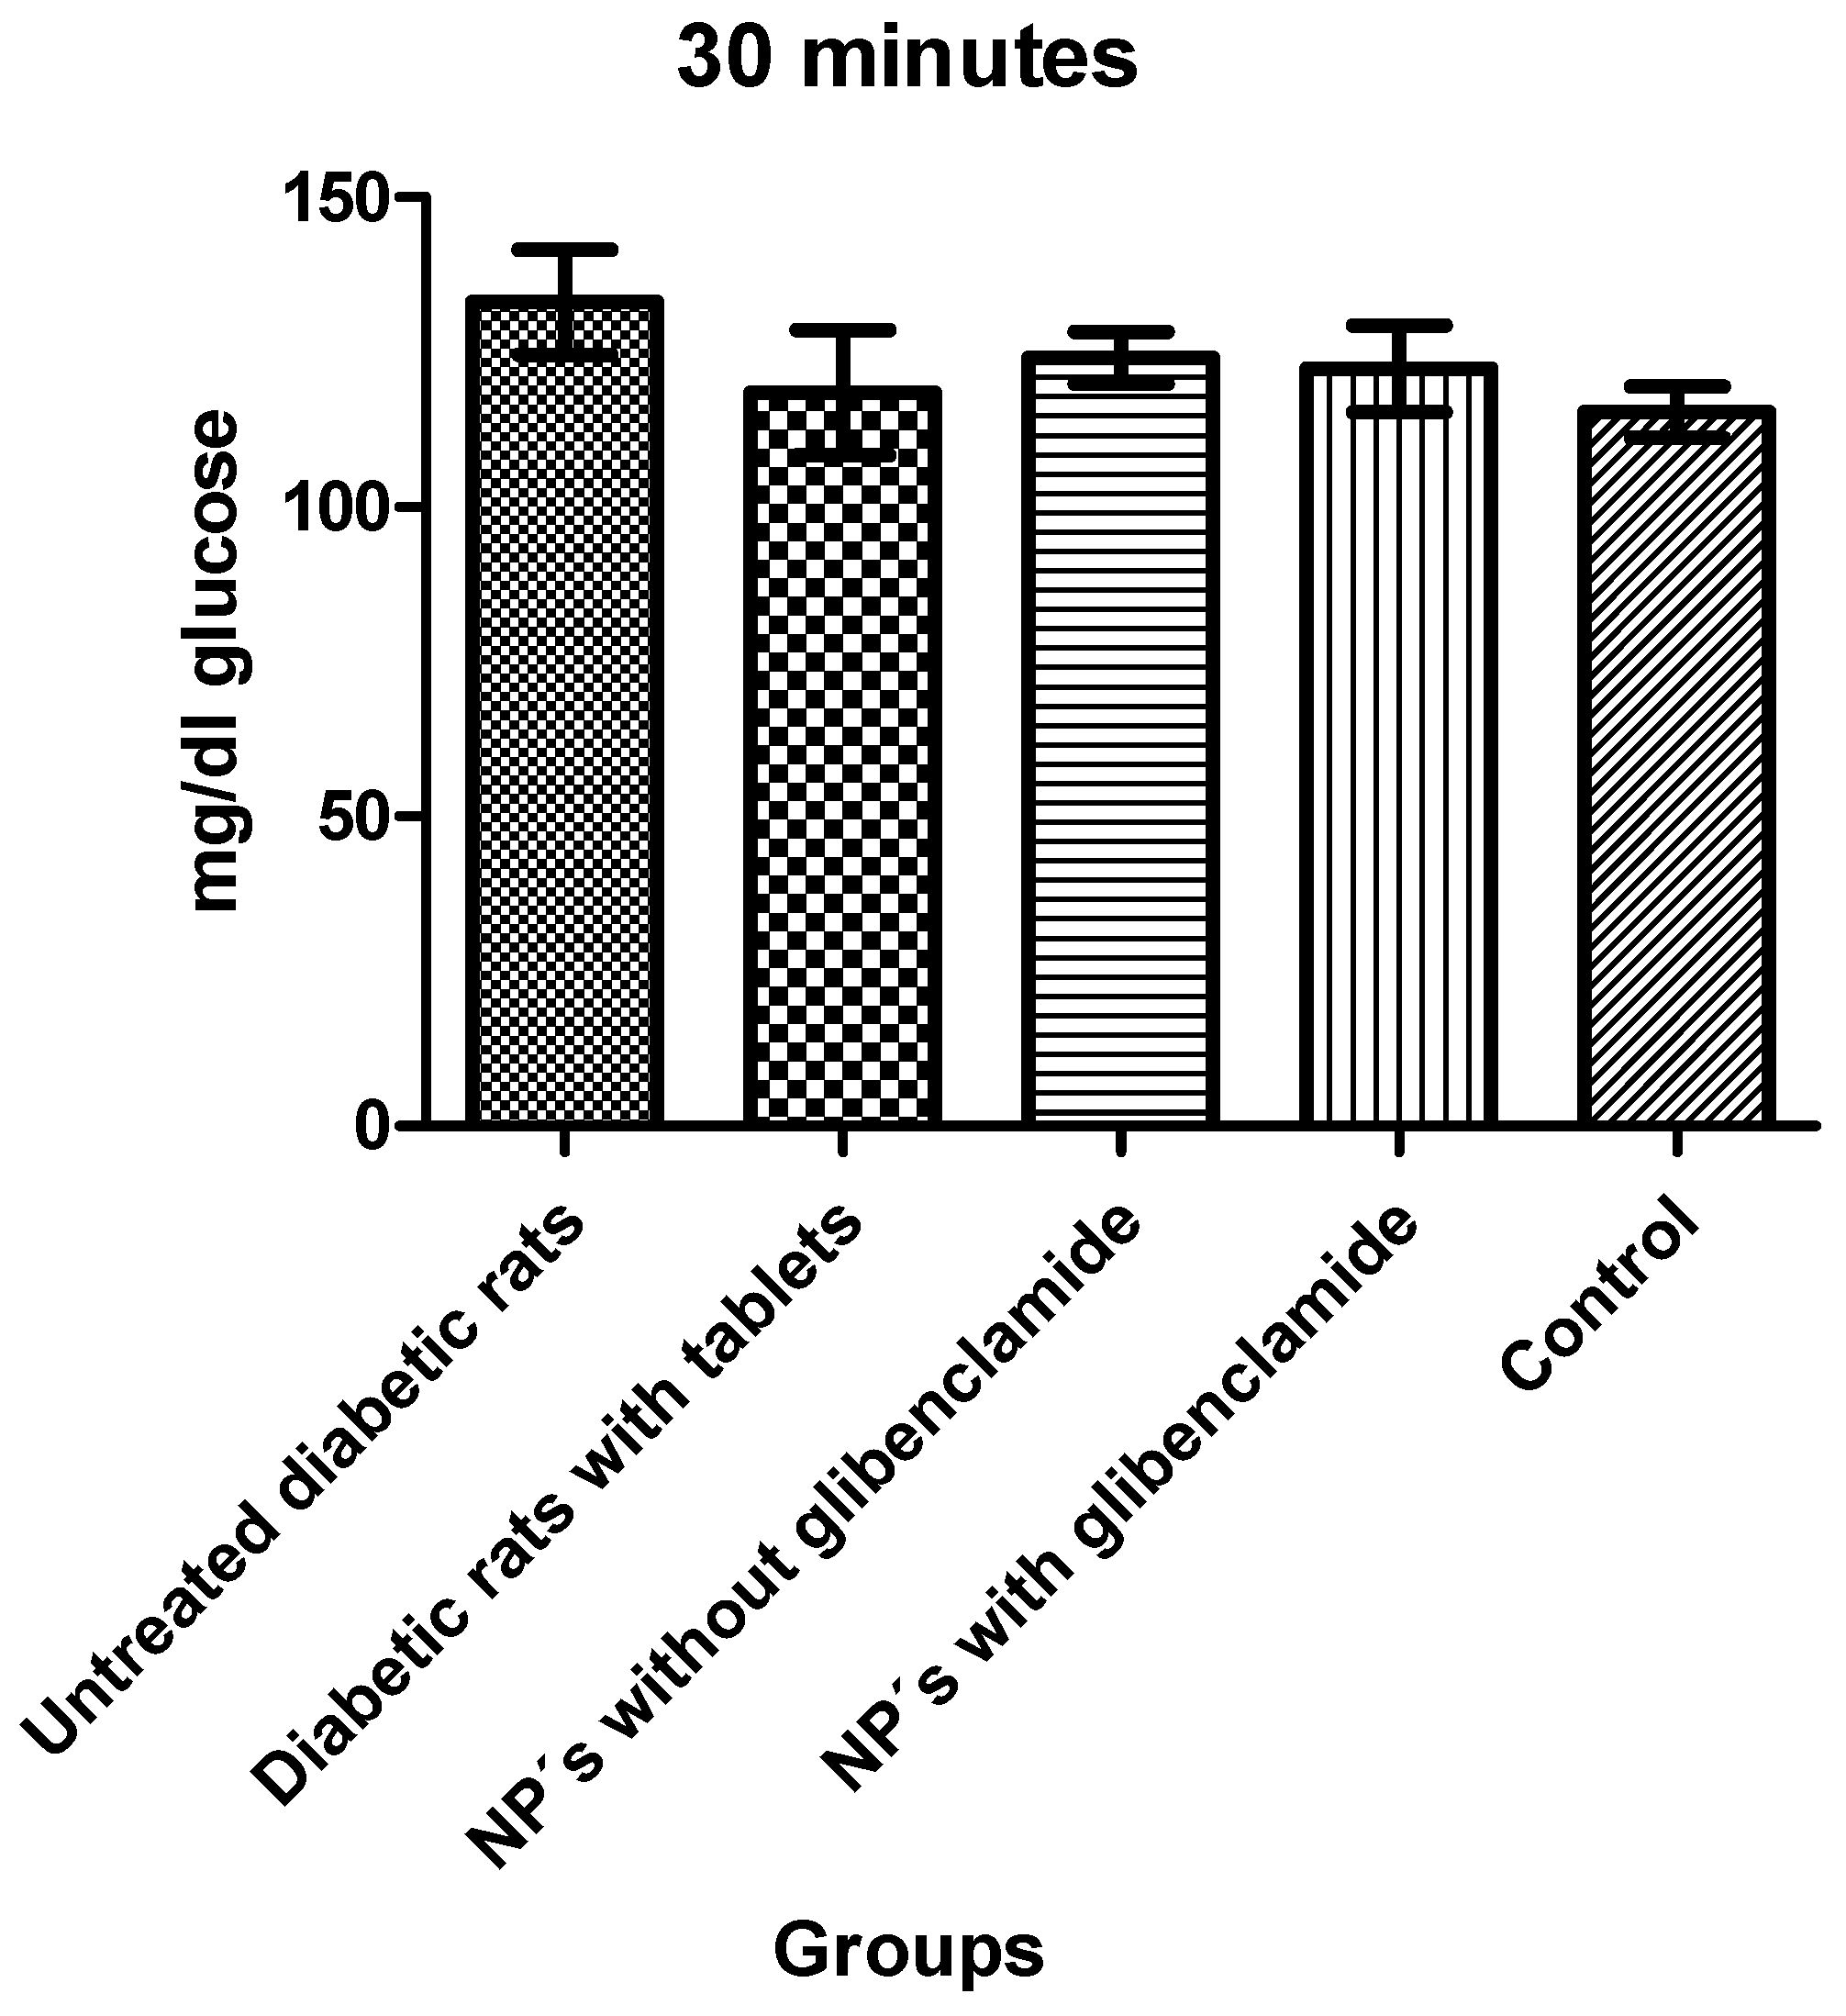

3.1.7. In Vivo Tests

| Animals Were Divided into 5 Different Groups with 5 Individuals Each as Follows: |

|---|

| Group 1: untreated diabetic rats |

| Group 2: diabetic rats with conventional pharmaceutical form (tablets) |

| Group 3: diabetic rats administered with NP without glibenclamide |

| Group 4: diabetic rats administered with NP with glibenclamide |

| Group 5: control |

| Tukey’s Multiple Comparison Test | Significant p < 0.05 | Summary | 95% CI of diff |

|---|---|---|---|

| Group 1 vs. Group 2 | Yes | *** | 15.42 to 61.18 |

| Group 1 vs. Group 3 | No | ns | −4.005 to 41.76 |

| Group 1 vs. Group 4 | Yes | *** | 11.52 to 57.29 |

| Group 1 vs. Group 5 | No | ns | −3.008 to 42.23 |

| Group 2 vs. Group 3 | No | ns | −41.30 to 2.460 |

| Group 2 vs. Group 4 | No | ns | −25.78 to 17.99 |

| Group 2 vs. Group 5 | No | ns | −40.29 to 2.919 |

| Group 3 vs. Group 4 | No | ns | −6.354 to 37.41 |

| Group 3 vs. Group 5 | No | ns | −20.87 to 22.34 |

| Group 4 vs. Group 5 | No | ns | −36.40 to 6.813 |